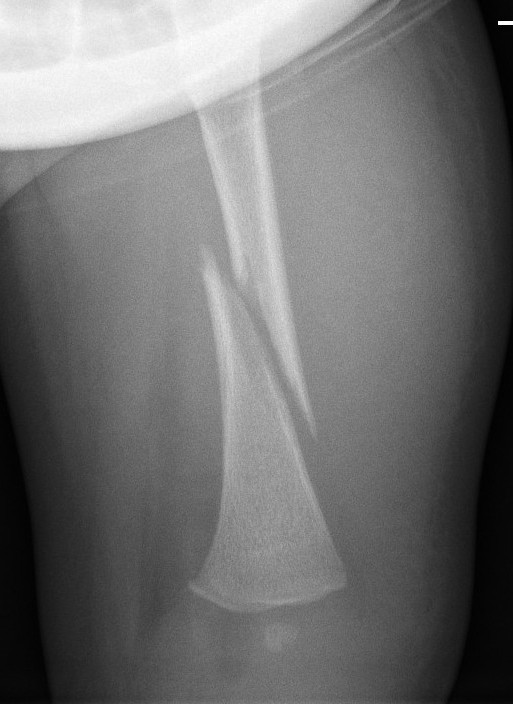

Spiral fracture of femur in a 3 month old which was the result of NAI. Note 'bucket handle' appearance of distal metaphysis